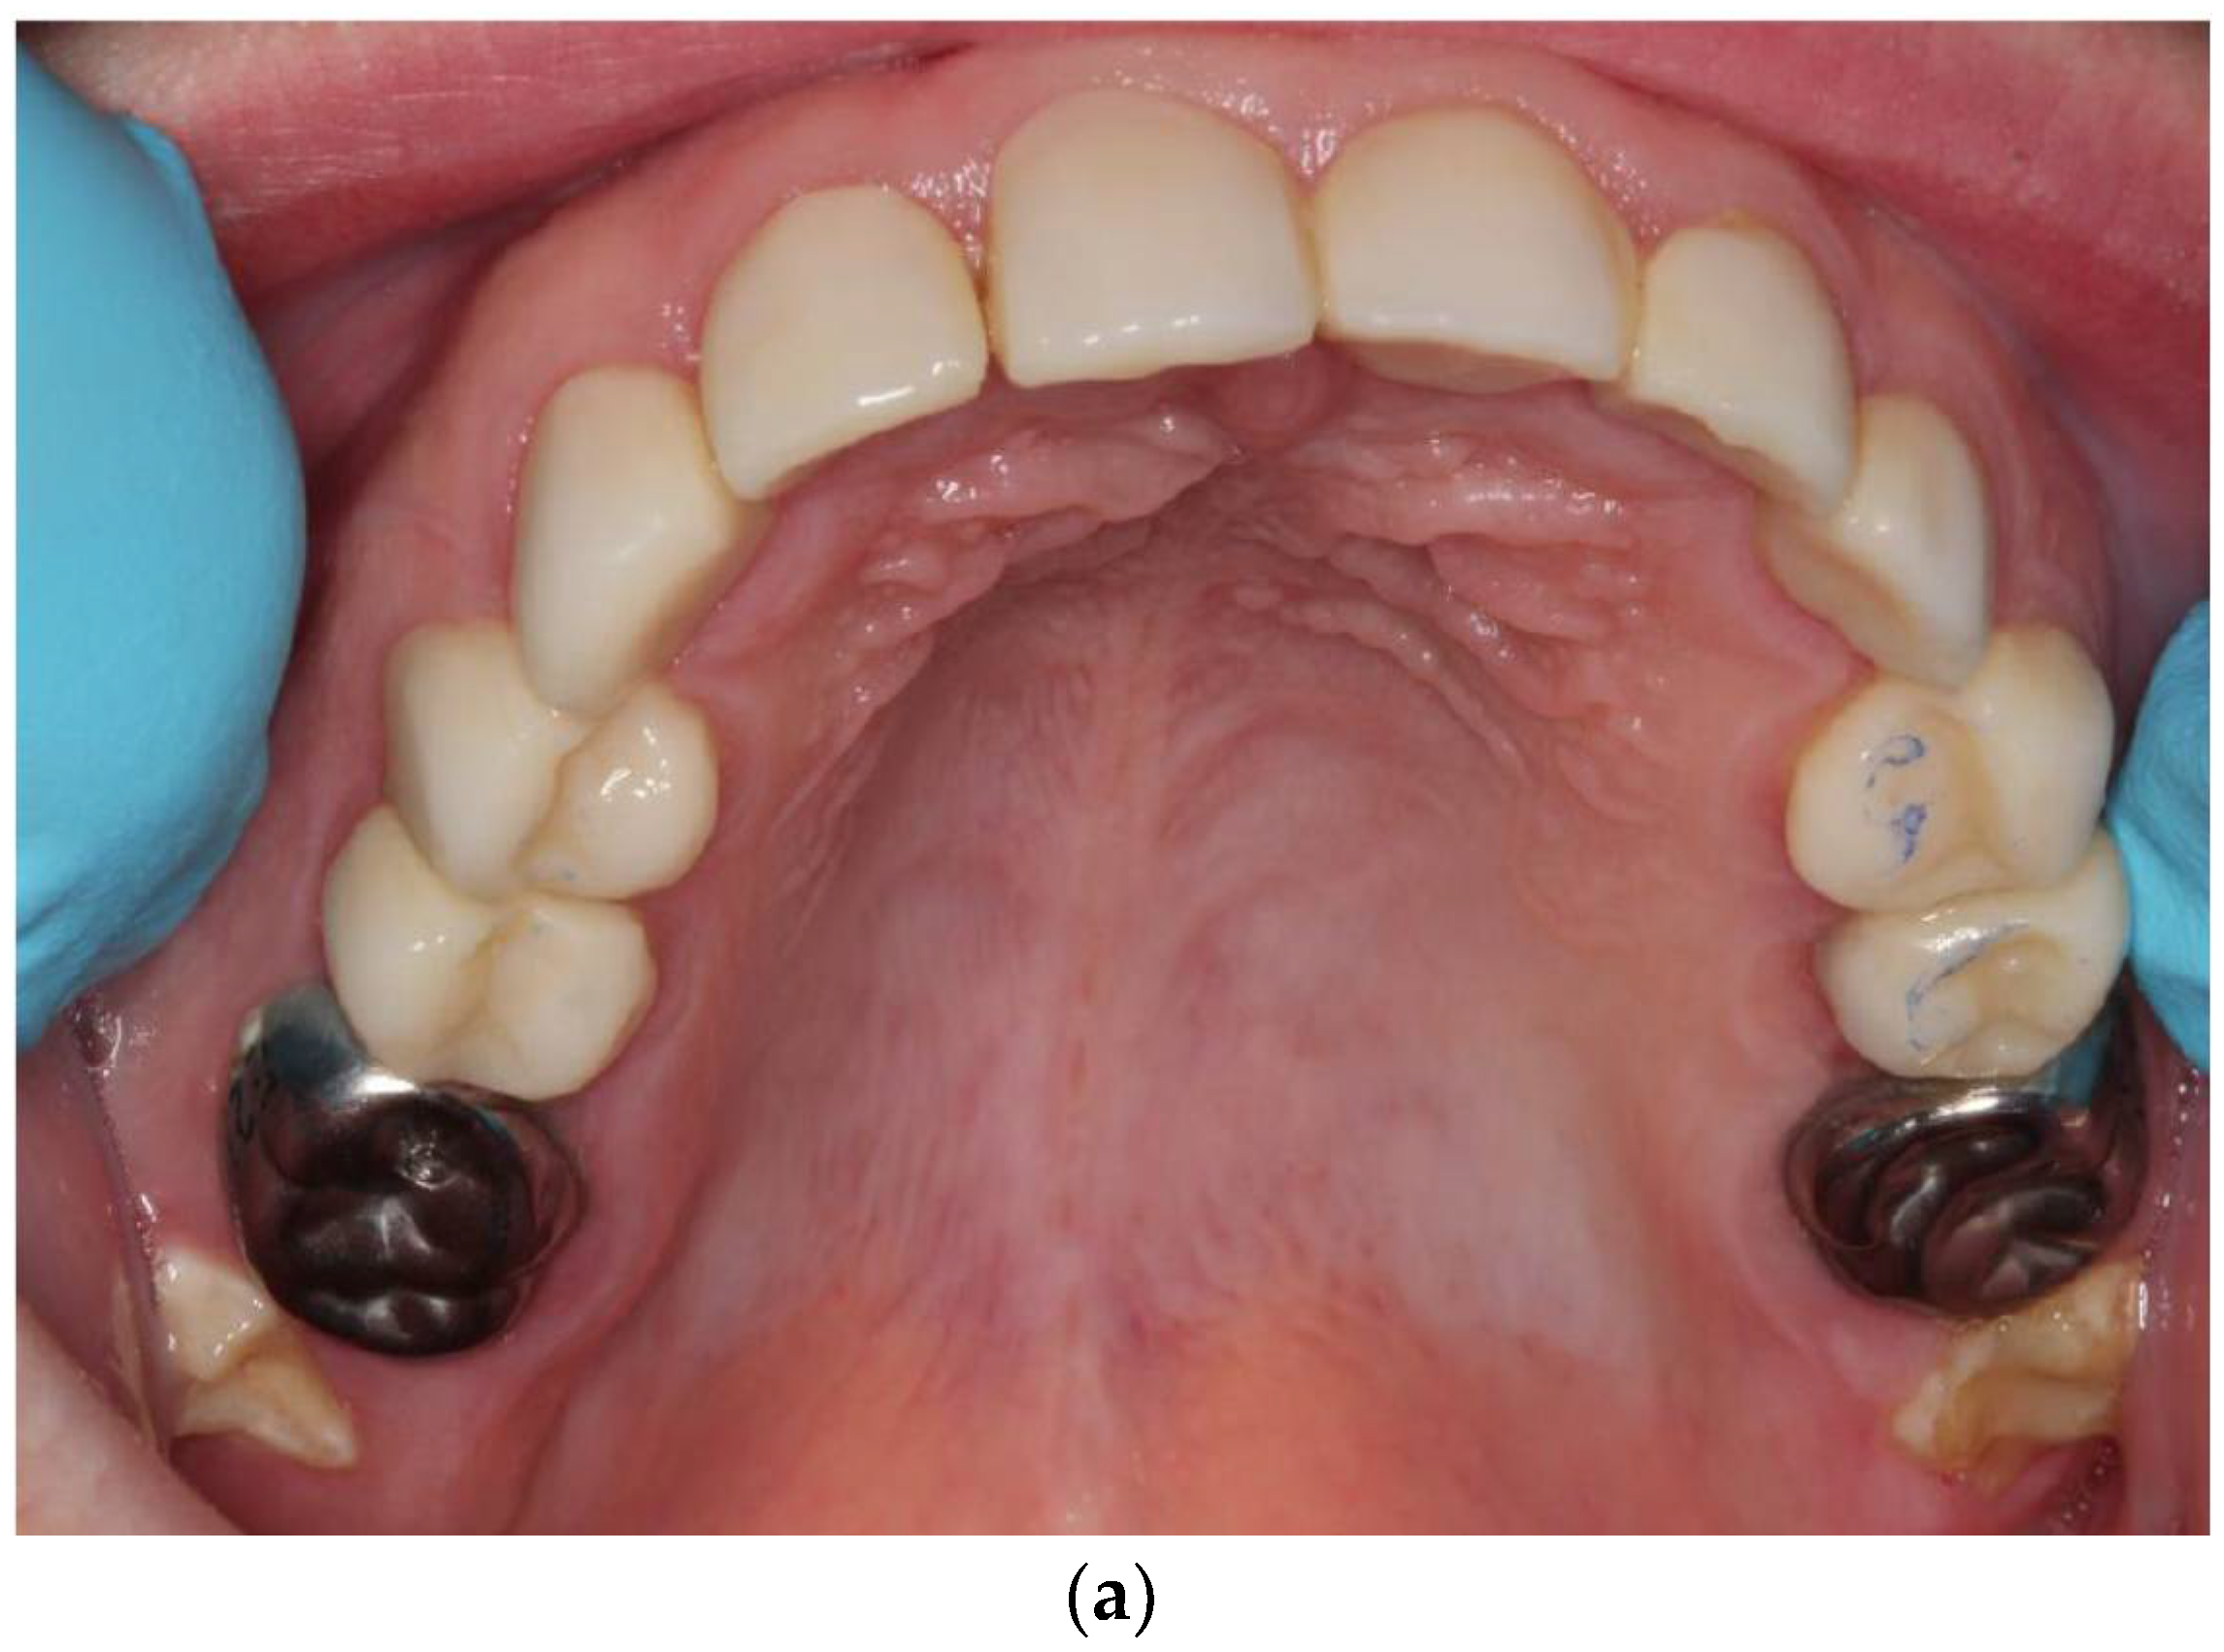

2.2. Case Report: Permanent Dentition